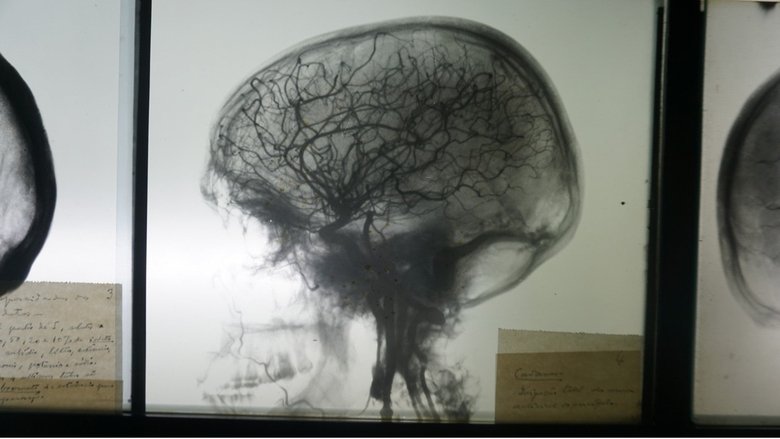

The history of prefrontal leucotomy, a brain intervention created by Portuguese neurosurgeon and scientist António Egas Moniz, Nobel Prize winner in Medicine.